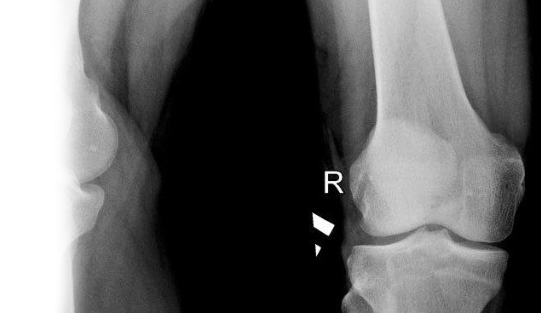

Рентгенография надколенника – важный метод прицельного исследования, который позволяет оценить состояние надколенника.

Диагностическая услуга выполняется в двух проекциях.

Рентген позволяет исключить патологию надколенника костно-травматического, дегенеративно-дистрофического генеза.